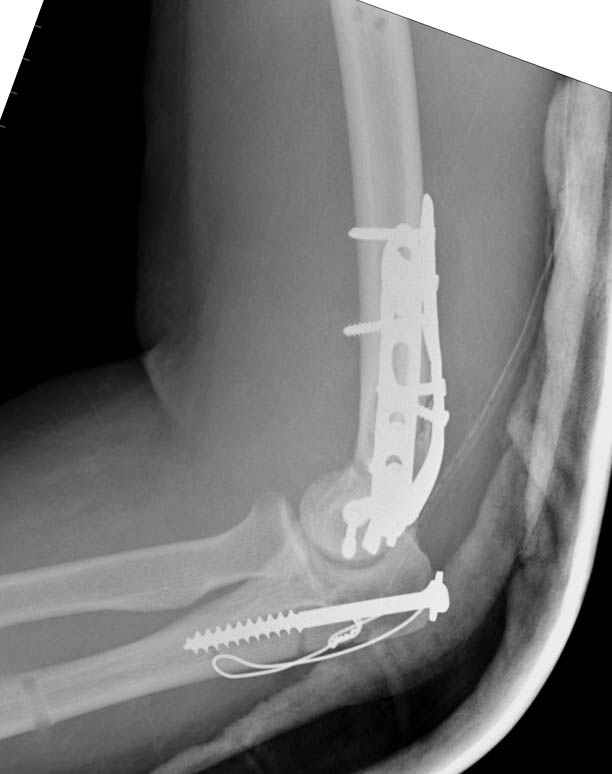

Djoldas Kuldjanov, M.D. 09 Сентябрь 2005, 20:07

Примерный случай, только перелом был открытый, в задне-медиальной стороне рана около 2 см по характеру "изнутри кнаружи", неврологический статус со слабостью сгибания мизинца, также слабая абдукция и аддукция указательного пальца и сгибания в кисти.

Больному сделали обработку и наложили временный аппарат внешной фиксации плечо-предплечье.

На шестой день сделали открытую репозицию чрезлоктевым доступом двумя locking plate, локтевой нерв был ушибленным, после операции положительная динамика в Flexor Carpi Ulnaris. Фиксацию локтевого отростка произвели tension band technique с дополнительным шурупом.

Этапы операции на снимках....

Джолдас Кульджанов